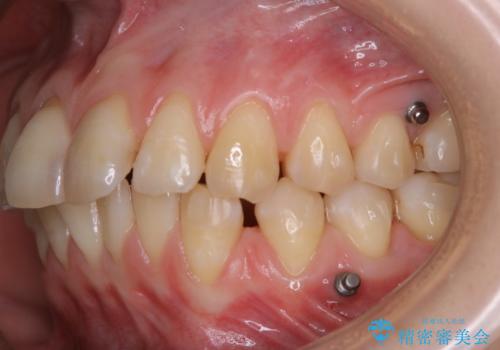

インビザラインでの治療中の患者様のクリーニング前後写真です。

- インビザライン矯正中に茶色が気になるとのことで来院されました。PMTC30分コースを行いました。

矯正治療中は虫歯や歯周病リスクが高くなります。